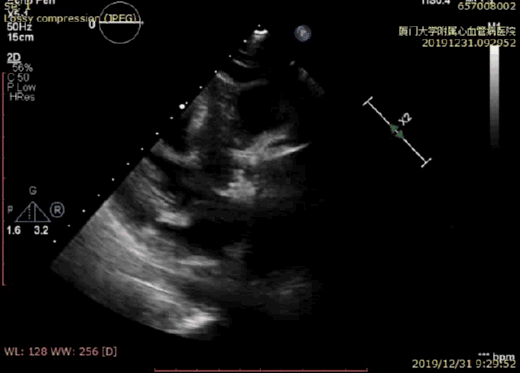

术后超声显示瓣膜位置良好

术后超声显示无瓣周漏